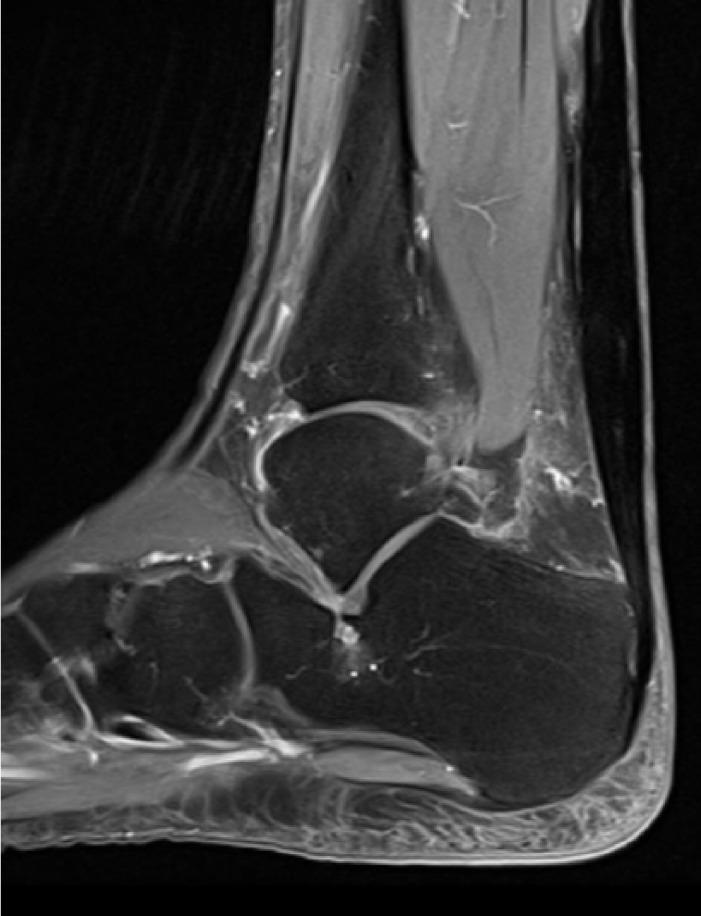

We reviewed and analysed this patient's records containing the sport-specific anamnesis, pre-existing condition, anamnesis of medications and therapy. The three injuries were magnetic resonance imaging-proven. Furthermore, the tendon's condition was examined histologically in the context of the operative treatment through lace technique of the Achilles tendon and transfer of the peroneus brevis to the peroneus longus. We also researched the literature for bilateral ruptures of the peroneal tendons.

我们回顾并分析了该患者的记录,包括运动专项病史、既往病史、用药史和治疗情况。这三处损伤均经磁共振成像证实。此外,在通过跟腱编织技术和将腓骨短肌转移至腓骨长肌进行手术治疗的过程中,对肌腱状况进行了组织学检查。我们还在文献中搜索了腓骨肌腱双侧断裂的病例。